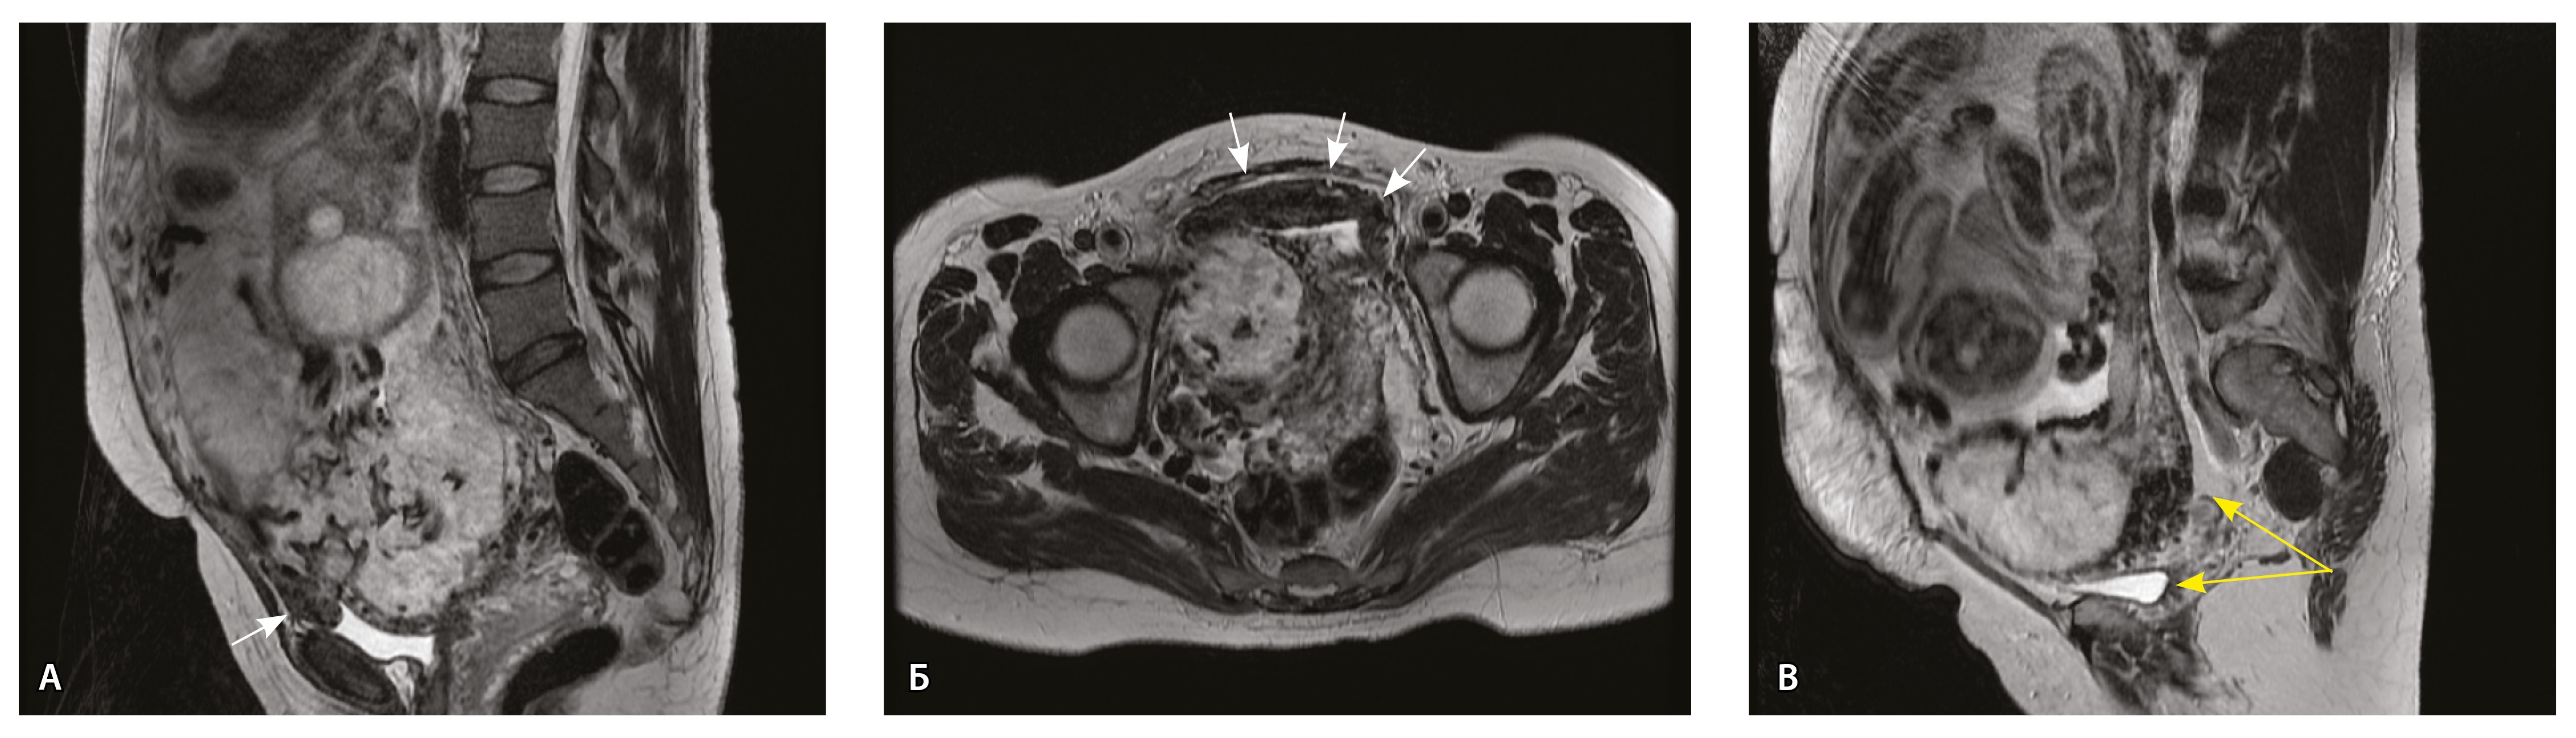

Сосуды 2-го типа. Единичные сливающиеся сосудистые полости в маточно-плацентарной области, мелкие ретроплацентарные гематомы, участки с белковым содержимым по МР-сигналу в зоне контакта ворсин со стенкой матки (рис. 4).

Рис. 4. Беременность 32 недели, pl. accreta, PAS 1 по FIGO. На магнитно-резонансных томограммах в режиме Т2-взвешенного изображения в сагиттальной (А) и аксиальной (Б) плоскостях видны сосуды на границе маточно-плацентарной области, сливающиеся между собой (белые стрелки), без выраженного дефицита толщины миометрия и рубца от кесарева сечения, без признаков выбухания стенки матки. На Т1-взвешенном изображении в режиме подавления сигнала от жировой ткани в аксиальной плоскости (В) выявляется наличие участков повышенного сигнала (желтые стрелки) на границе маточно-плацентарной области, что соответствует геморрагическому компоненту в подострой/хронической стадии (ретроплацентарные гематомы) либо белковому содержимому (фибриноид)

Непосредственное сравнение МР-картины с операционным материалом подтвердило, что полости с геморрагическим компонентом соответствовали ретрохориальным гематомам различной давности, чаще подострой и хронической стадий, которые состояли из гемолизированных эритроцитов, нитей фибрина сетчатого строения, а также замурованных атрофичных ворсин (рис. 5). Следовательно, констатация на МРТ фиксированных геморрагических полостей в маточно-плацентарной области отражает не гиперваскуляризацию стенки матки, а наличие ретрохориальных гематом в подострой/хронической стадии, что следует учитывать в клинической практике.

Рис. 5. Сосуды 2-го типа при гиперваскуляризации стенки матки при патологической инвазии: А – организованная ретрохориальная гематома в маточно-плацентарной области, в ее составе много инволютивных якорных ворсин (окраска по Маллори; × 100); Б – в составе гематомы видна пролиферация цитотрофобласта (иммуногистохимическое исследование, маркер цитокератин 8; × 100)

Как видно на рис. 6, сосуды 2-го типа не встречались в норме и при плотном прикреплении плаценты (gr 2), с одинаковой частотой наблюдались при pl. accreta (gr 3) и pl. increta (gr 4) и были обнаружены у 94,4% пациенток с pl. percreta (gr 5) (р < 0,001, хи-квадрат Пирсона).

Рис. 6. Частота встречаемости сосудов 2-го типа при различной глубине приращения плаценты (grade МАPI-RADS)

Сосуды 3-го типа. Внутриматочная гиперваскуляризация с дефицитом толщины миометрия, преимущественно сосуды срединного слоя, аналог pl. increta PAS 2, гестационная перестройка радиальных артерий (рис. 7).

Рис. 7. Беременность 34 недели, pl. increta, PAS 2 по FIGO. На магнитно-резонансных томограммах в режиме Т2-взвешенного изображения в сагиттальной (A, Б) и фронтальной (В) плоскостях определяется внутриматочная гиперваскуляризация с наличием многочисленных сливающихся сосудов в толще стенки матки, в области плацентарной площадки (белые стрелки); в нижнем маточном сегменте – выраженное истончение стенки матки, рубца от кесарева сечения с формированием маточной грыжи (желтые стрелки)

При pl. increta наличие патологических сосудов на изображениях МРТ связано с неполной гестационной перестройкой радиальных артерий, расположенных в срединном слое миометрия. Так, при окраске по Маллори они определяются как сжатые комплексы артерий среднего калибра, с частичным замещением внутренних слоев стенки матки, темно-красными фрагментами плодного фибриноида. На серийных срезах видно, что в этой артерии присутствует достаточное количество инвазивного цитотрофобласта (маркер цитокератин 8), но предыдущий срез подтверждает замещение мышечной оболочки фиброзной тканью как в стенке радиальной артерии, так и в периартериальном пространстве (рис. 8).

Рис. 8. Сосуды 3-го типа при гиперваскуляризации стенки матки при патологической инвазии. Внутриматочная гиперваскуляризация с дефицитом толщины миометрия, наличием рубцовой ткани, недостаточная гестационная перестройка радиальных артерий (аналог pl. increta, PAS 2 по FIGO). А – неполная гестационная перестройка радиальной артерии в составе миометрия (окраска по Маллори; × 50); в верхней части просвета артерии виден слой фибриноида, замещающего эндотелий, такой же фрагмент – в нижней части артерии (стрелка); Б – серийный срез той же радиальной артерии с визуализацией инвазирующего цитотрофобласта (маркер цитокератин 8; × 50); В – серийный срез той же радиальной артерии, при окраске на выявление эластических волокон видна полная дезорганизация эластического каркаса вместо нормальных внутренней и внешней эластических мембран, результат действия инвазирующего цитотрофобласта (окраска по Вейгерту; × 50)

При анализе частоты встречаемости сосудов 3-го типа в зависимости от степени приращения плаценты (рис. 9) отмечается преобладание данного типа сосудов при глубоких вариантах инвазии плаценты – pl. increta (gr 4), pl. percreta (gr 5) – и отсутствие их при плотном прикреплении плаценты (gr 2) и поверхностном приращении (pl. accretа, gr 3) (р < 0,001, хи-квадрат Пирсона).

Рис. 9. Частота встречаемости сосудов 3-го типа при различной глубине приращения плаценты (grade МАPI-RADS)